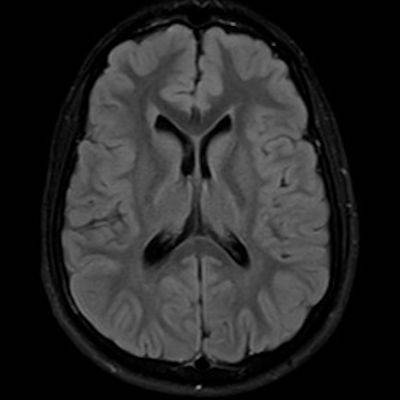

11 ay, Nöbet

Charlevoix-Saguenay Otozomal Resesif Spastik Ataksisi (ARSACS)

Charlevoix-Saguenay Otozomal Resesif Spastik Ataksisi ARSACS

ARSACS (Charlevoix-Saguenay otozomal resesif spastik ataksisi) Sendromu

Serebellar folya sinapsisi